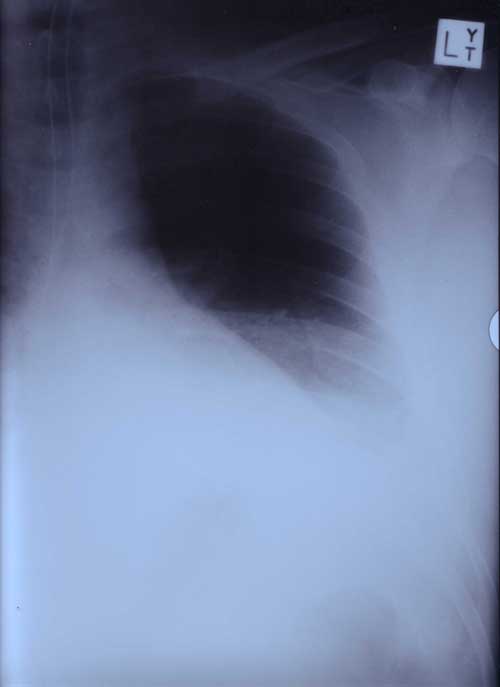

22nd January 2000